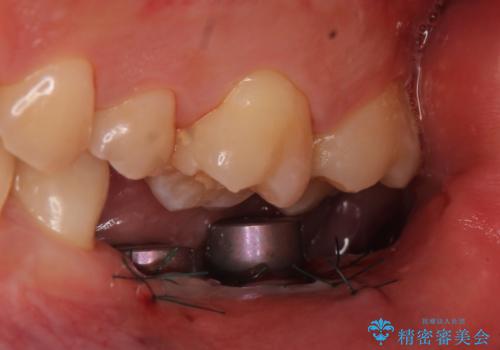

- 数年前に左下の奥歯を2本失ってから物が咬めないため何とかして欲しいと当院にいらっしゃった方の症例です。

左下にインプラント(ストローマン)を2本埋入し、オールセラミッククラウンによる補綴を行いました。

カスタムアバットメントは患者様それぞれの歯茎に合わせて製作されたオーダーメイドのアバットメントです。

既製のアバットメントに比べ適合がよく、高い清掃性を誇ります。